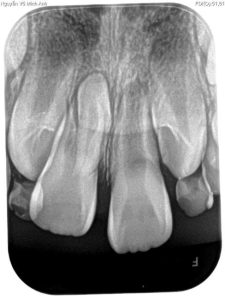

- Thăm khám & Chụp phim (X-quang/CT Cone Beam): Đây là bước quan trọng nhất để xác định chính xác vị trí, hình dáng và mức độ ảnh hưởng của răng thừa đối với các chân răng xung quanh.